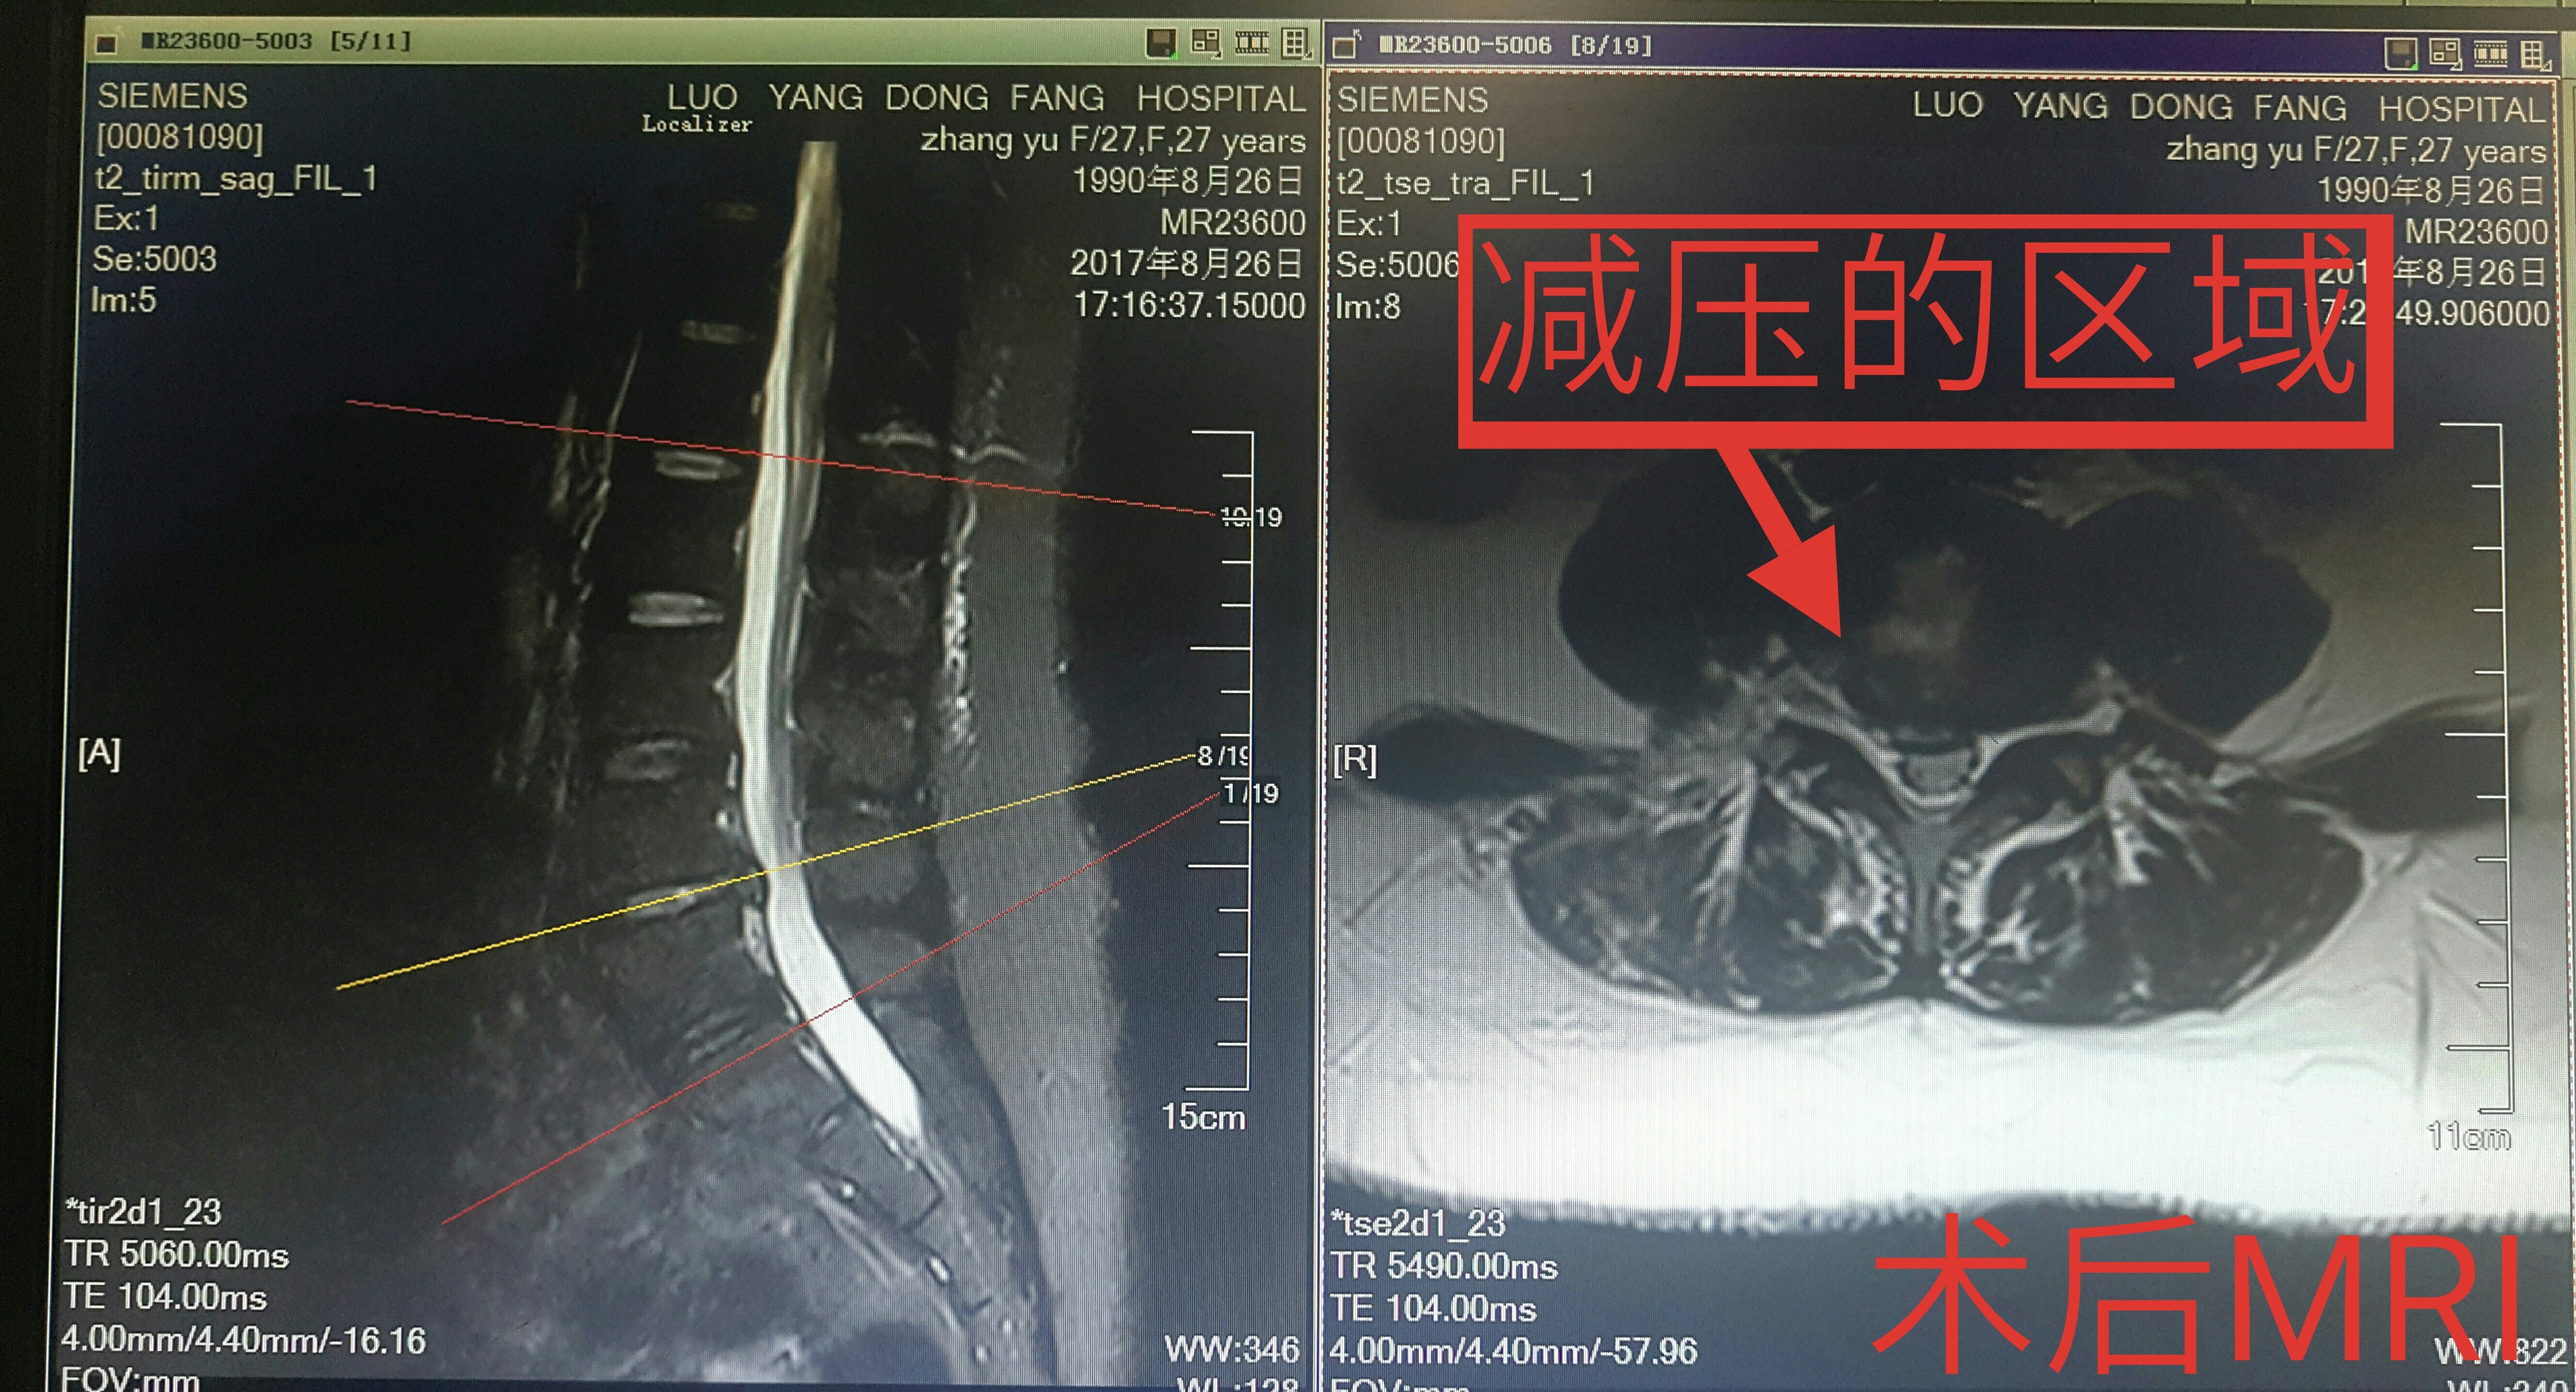

脊柱内镜翻修腰椎间盘突出症胶原酶溶核术后复

4002x3272 - 1704KB - JPEG

脊柱内镜翻修腰椎间盘突出症胶原酶溶核术后复

5312x3984 - 3620KB - JPEG

脊柱内镜翻修腰椎间盘突出症胶原酶溶核术后复

5130x2828 - 2342KB - JPEG